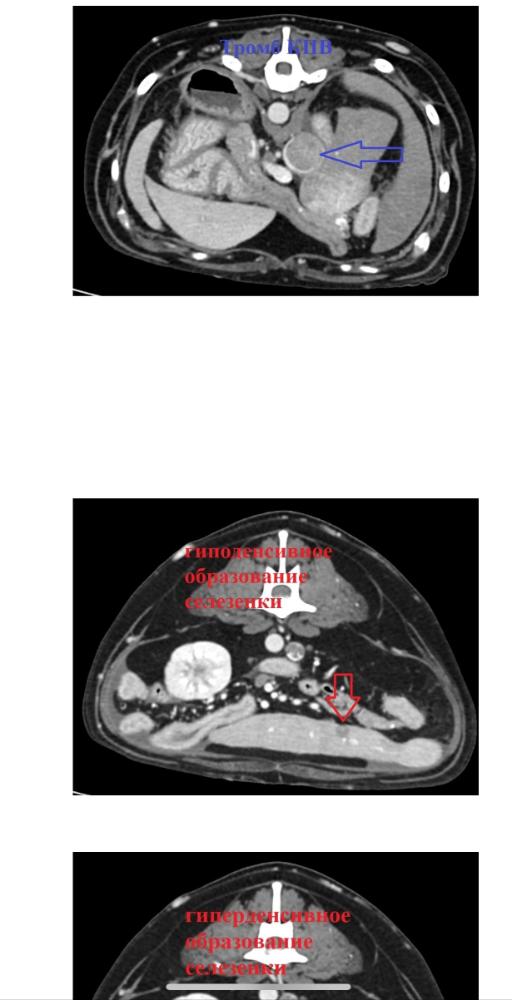

Дорогие форумчане, с Вилли случилась беда!!!🆘

Вилли разбил инсульт, 23.02 мальчик встал на кровати, пошатываясь, попытался спрыгнуть, но потерял сознание и нырнул в бессознательном состоянии на пол, тывнувшись носом с этой высоты в пол ((( Выбито 4 зуба. Сделали еще УЗИ - нашли образования в надпочечнике и печени, еще разные вопросы. 😔 Целый букет!

Сейчас мальчик был на КТ, ждем результаты. Когда падал с кровати без сознания, сломал об пол 4 зуба. Удалили их под седацией сейчас, поскольку давать полноценный наркоз чревато. Теперь надо обращаться к терапевтам за грамотной терапией, чтобы поддержать ребенка на сколько возможно. Там букет, боюсь, что на КТ откроется еще более страшная картина.

Получили описание  КТ и свежие анализы крови 😔 Множество образований, показатели крови ухудшаются...